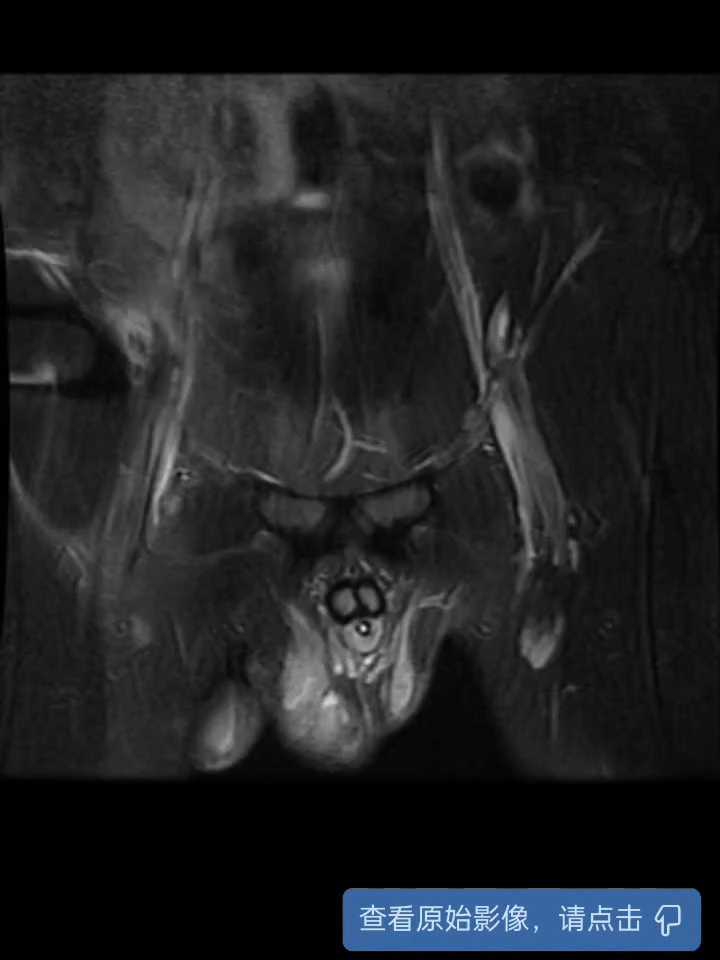

盆腔增强CT

磁共振增强